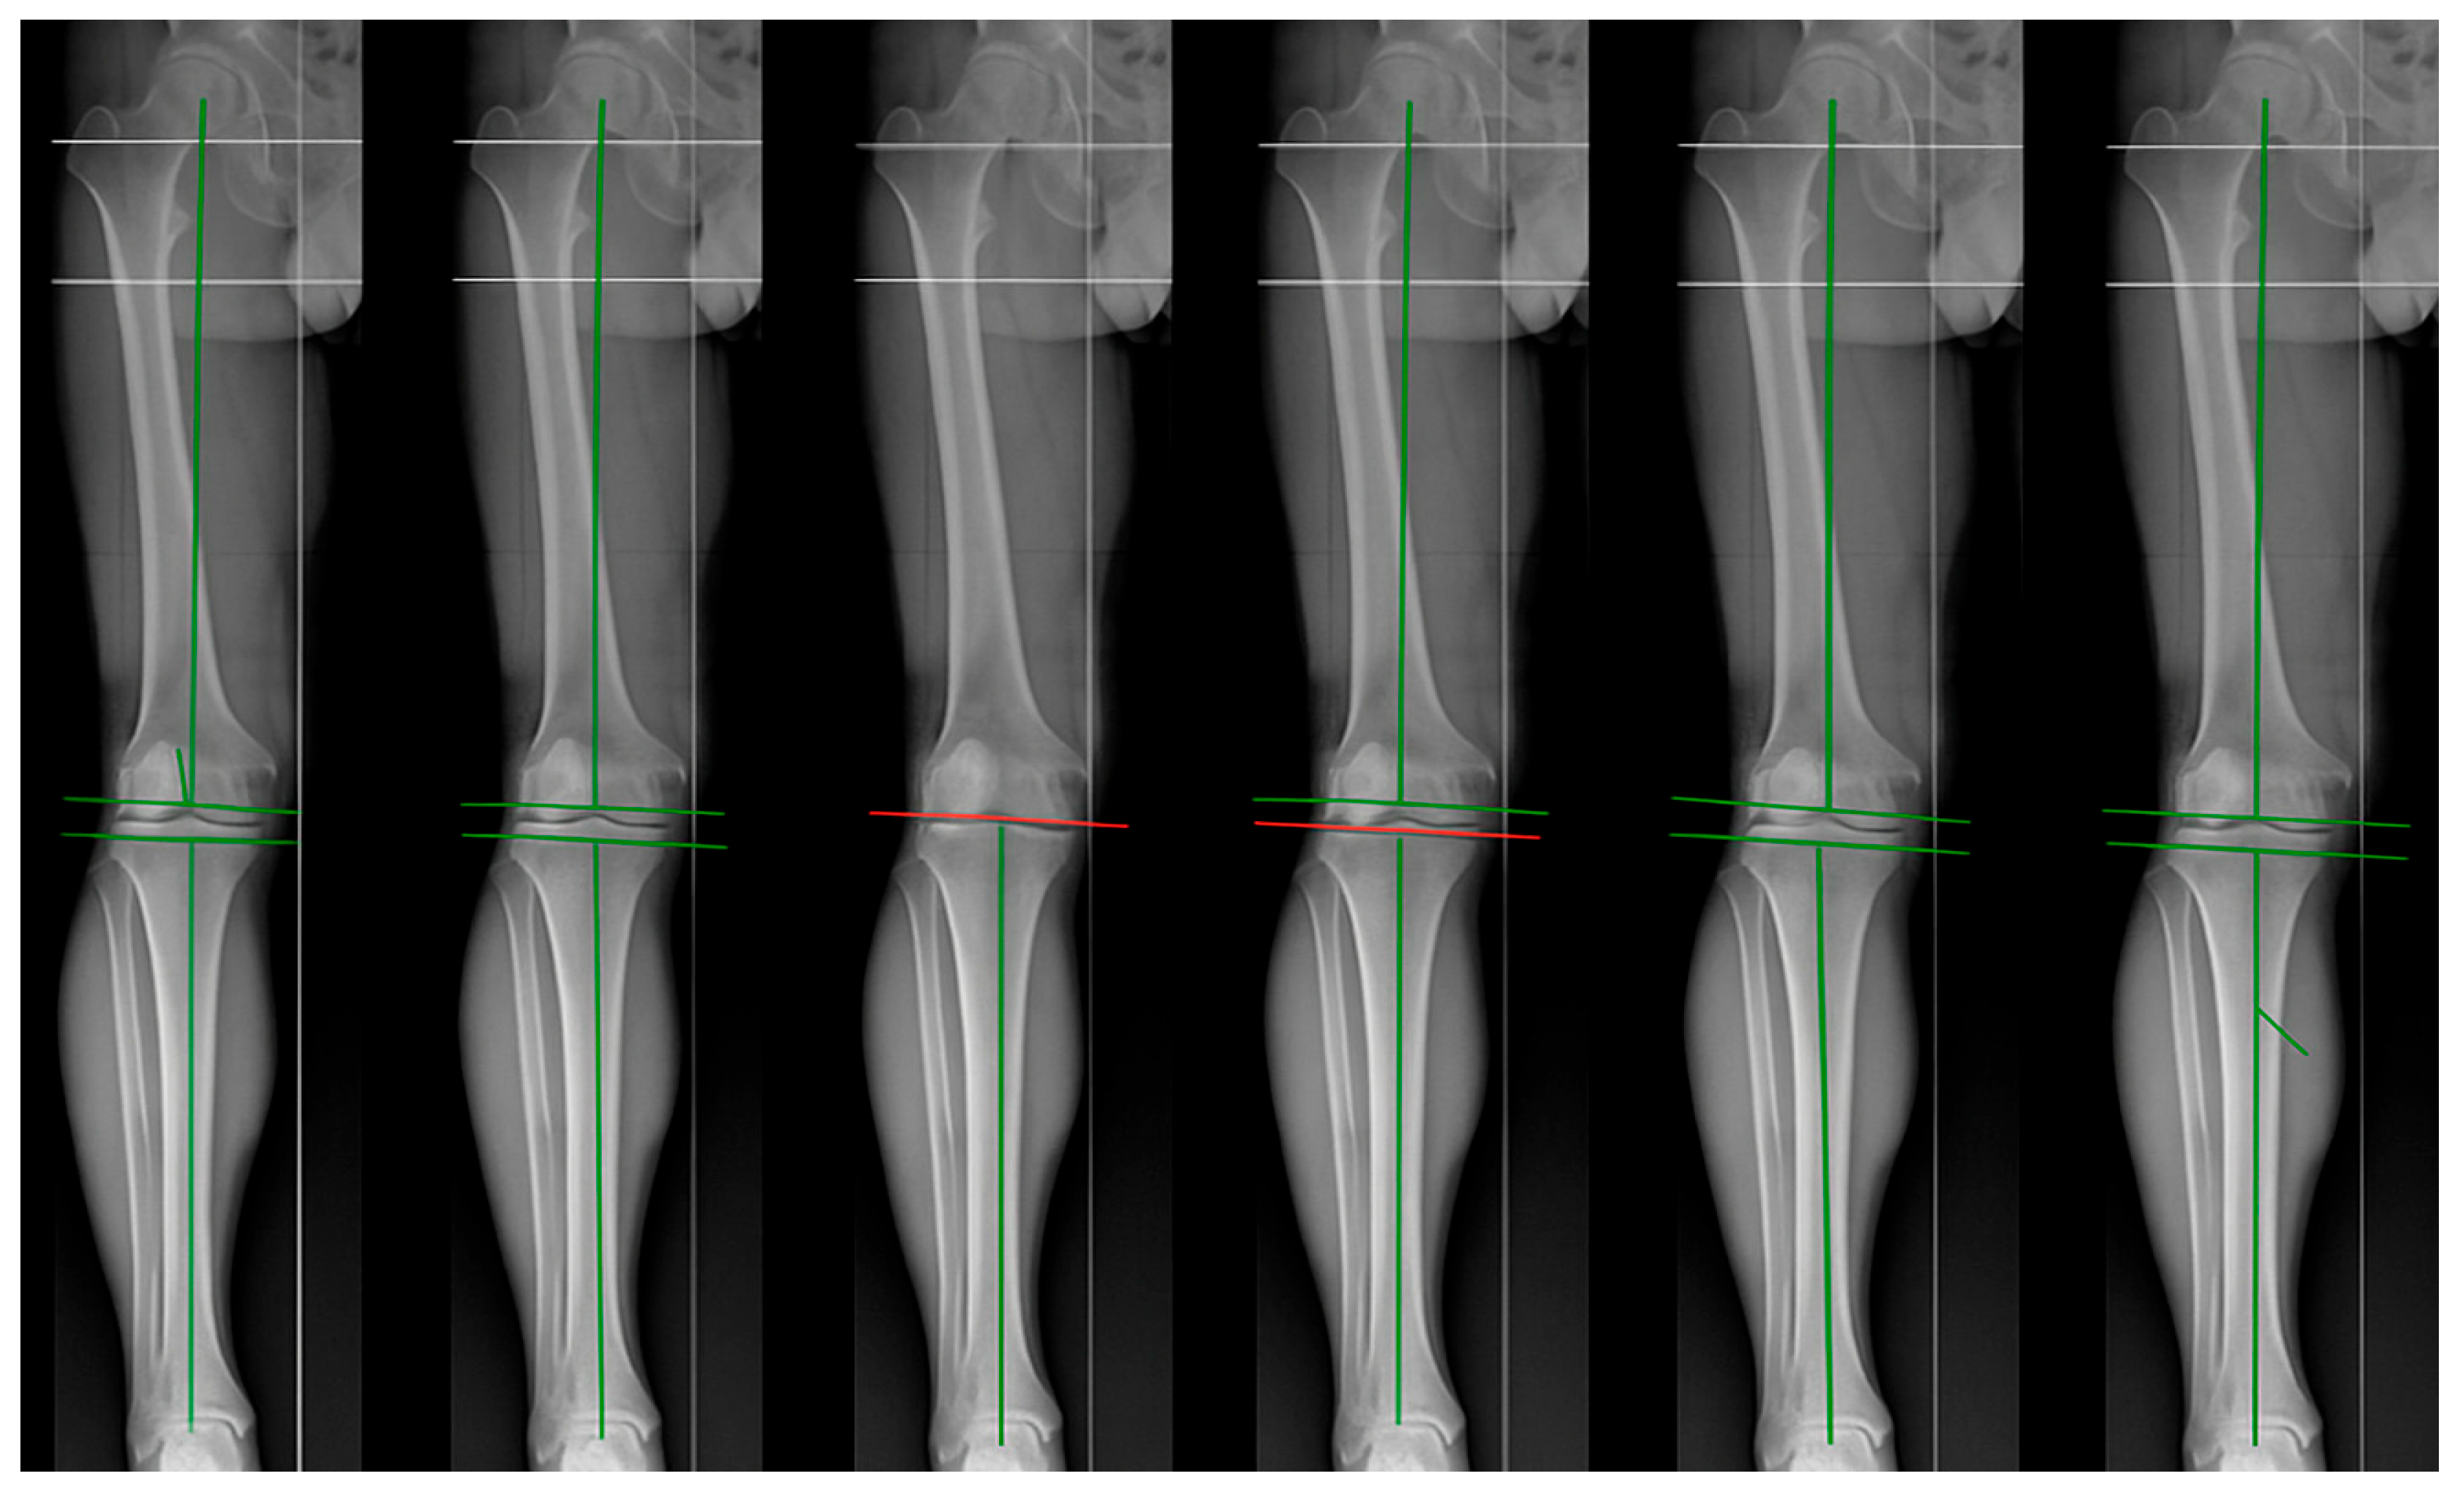

2. Mechanical Alignment

3. Anatomical Alignment

4. Adjusted Mechanical Alignment

5. Kinematic Alignment

6. Restricted Kinematic Alignment

7. Inverse Kinematic Alignment

8. Functional Alignment